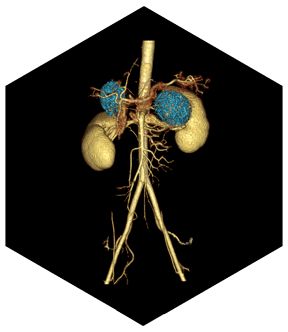

- Расширенный коронарный анализ

- Определяет степень стеноза и состав бляшки коронарной артерии, помогает при послеоперационном осмотре при шунтировании и стентировании

- Полностью автоматическая сегментация

- Полностью автоматическое извлечение

- Автоматическое обозначение кровеносных сосудов

- Анализ стеноза коронарной артерии

- Несколько интерактивных инструментов

- Удаление и измерение коронарных артерий с помощью искусственного интеллекта